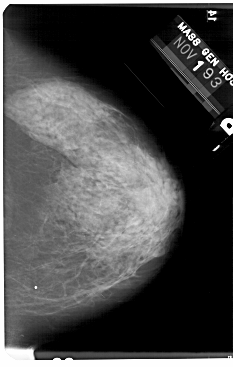

A_1732_1.LEFT_CC

LEFT_CC LINES 5491 PIXELS_PER_LINE 3511 BITS_PER_PIXEL 12 RESOLUTION 43.5 OVERLAY